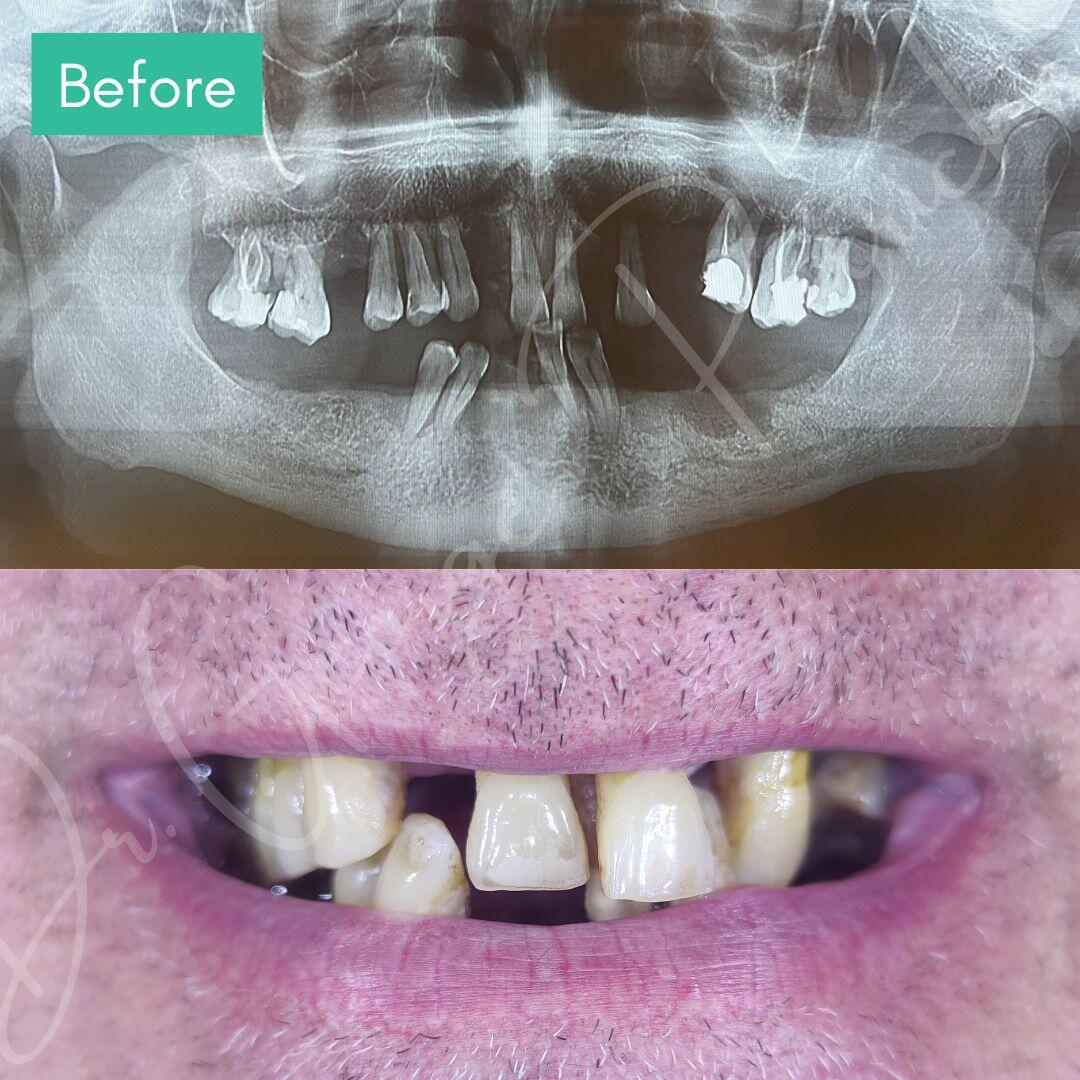

Before & After